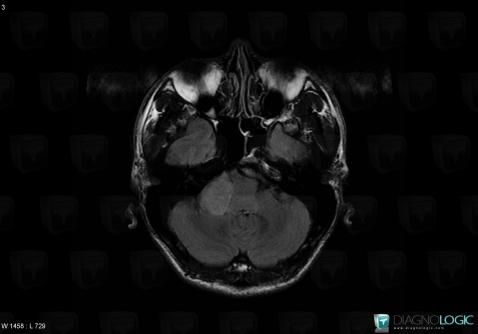

Schwannome, Espaces peri cérébraux infratentoriels, Autres nerfs craniens, IRM

Voici les informations spécifiques à l'image clé ci dessus:

- Diagnostic Schwannome, Localisation(s) Autres nerfs craniens, comportant les gammes Lésion des nerfs craniensEspaces peri cérébraux infratentoriels, comportant les gammes Lésion extra axiale infra tentorielleFosse postérieure, comportant les gammes Lésion infratentorielle en hypersignal T2 ou FLAIR